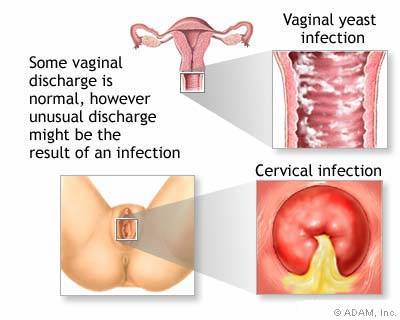

รูปที่ 1 โรคมรณะอย่างมะเร็งปากมดลูกอาจนำมาด้วยอาการเพียง “ตกขาว” หรือมีเลือดออกกะปริดกะปรอยเท่านั้น

รูปที่ 7 ตกขาวสีเหลืองหรือเขียวร่วมกับมีกลิ่นผิดปกติเป็นสัญญาณเตือนของการติดเชื้อภายใน